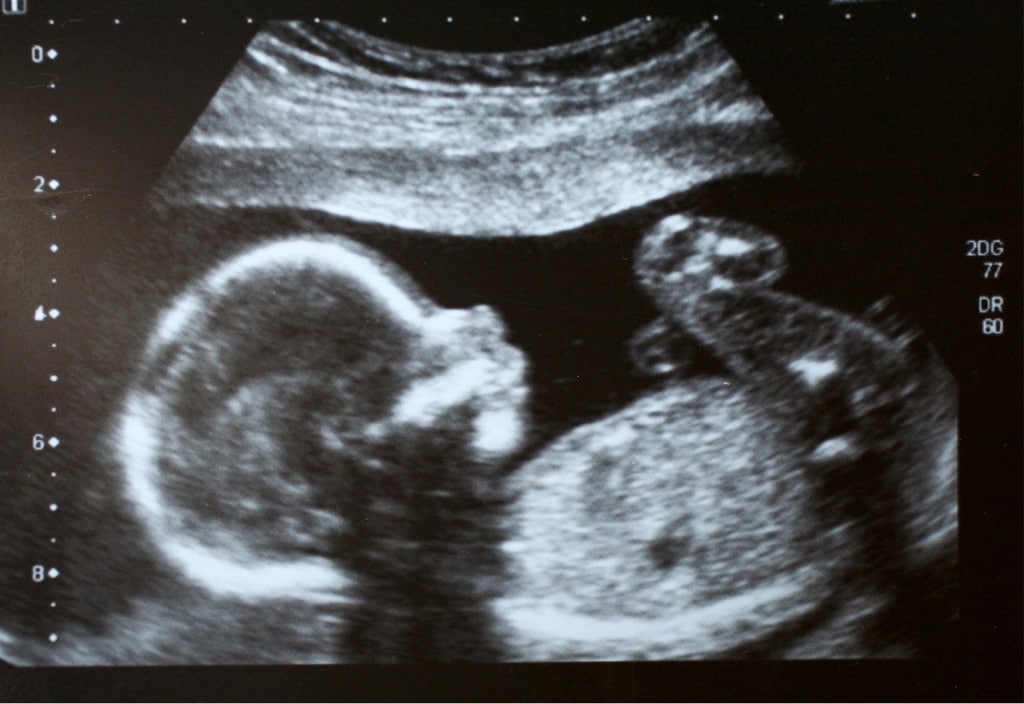

Prenatal testing is genetic testing performed in pregnancy to look for genetic conditions in the developing fetus. Prenatal testing includes two types: screening tests to determine your likelihood of having a child with a genetic condition, or diagnostic testing involving an invasive procedure to provide a definitive diagnosis.

We value the importance of providing non-judgmental supportive genetic advice urgently whenever concerns in pregnancy occur, such as prenatal testing or screening results, fetal structural or genetic changes or family history of a genetic condition. We aim to provide the information that you need to make an informed choice regarding concerns in your pregnancy.